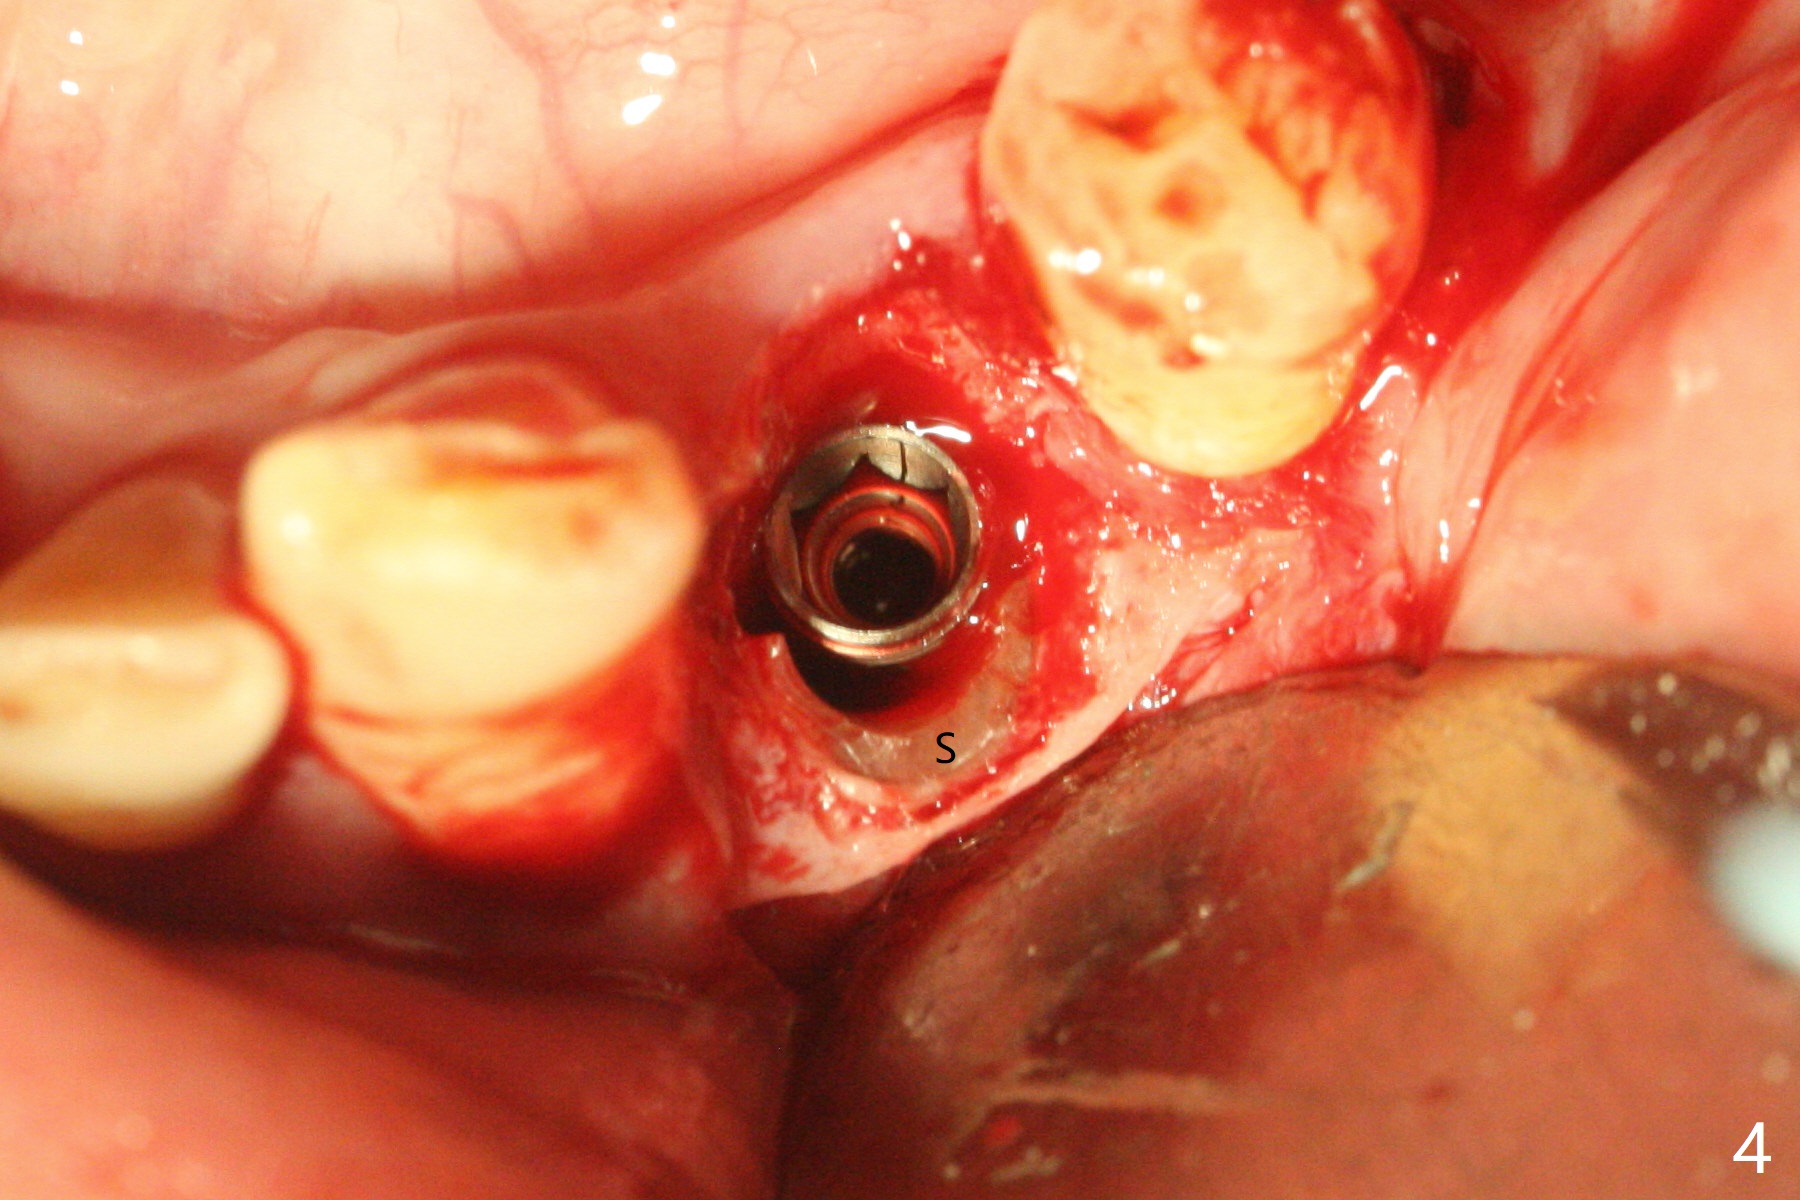

Since the root surface at #29 is distinct (Fig.1), while that at #21 is not (with subgingival caries, Fig.2), closed and open socket shields are done at #29 and 21, respectively (Fig.3,4 S), followed by implant placement with guide (Fig.4-6). With socket shield, there is limited remaining space for bone graft (Fig.4). The shield associated with the closed technique is exposed nearly 2 months postop (Fig.7), while the one associated with the open technique is not (Fig.8). The buccal plate is minimally atrophic with either technique.